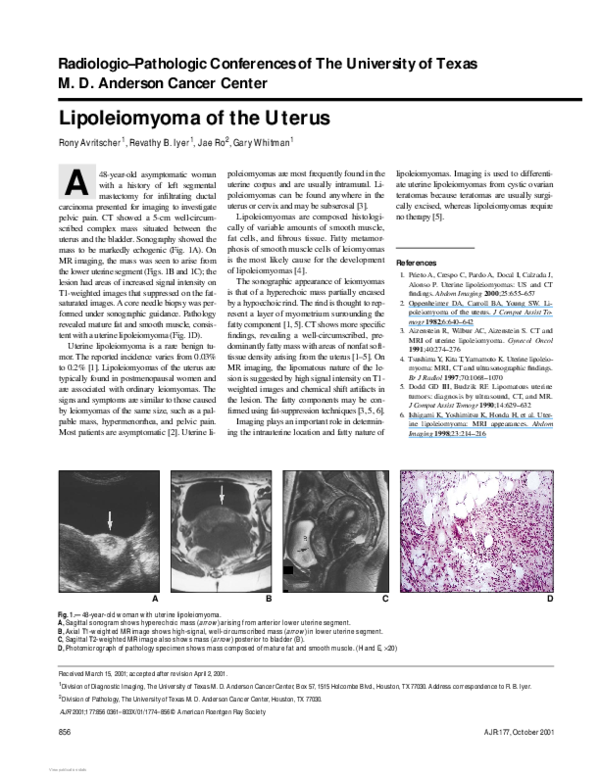

Pdf Lipoleiomyoma Of The Uterus Ezio Fulcheri Academia Edu